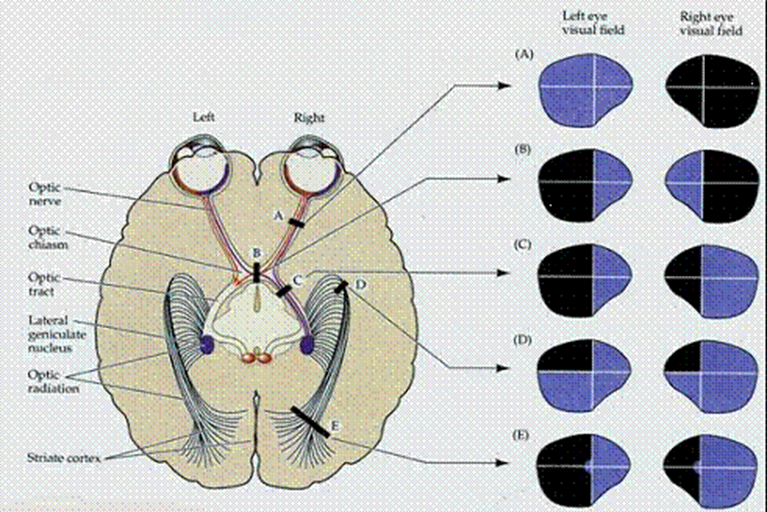

Hemianopsie is een vermindering van je gezichtsveld met beide ogen.

Omdat de hersenbloeding aan de rechterkant van mijn hoofd zat, zijn de zenuwbanen die van mijn linker netvliezen (linker-en rechteroog) naar de hersenen gaan beschadigd. De ogen zijn dus goed, alleen de vertaling van wat je ziet in je linker-gezichtsveld komt niet aan.

In mijn geval is situatie E van toepassing